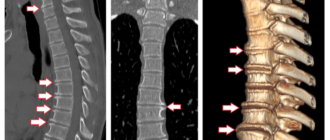

Нарушение статики позвоночника при остеохондрозе: симптомы и лечение Остеохондроз – это ведущая причина нарушения

Деформирующий остеохондроз: причины, симптомы, лечение Деформирующим остеохондрозом называется мультифакториальное заболевание, которое характеризуется разрушением анатомических